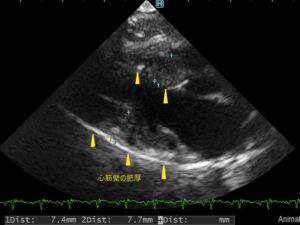

11歳のねこちゃんがわんにゃんドックのCコースを受けていただいた際に、心不全マーカー(proBNP)の上昇が認められました。症状はなく、心雑音もありませんでしたが、後日心臓超音波検査を行ったところ心筋壁が肥厚しており、肥大型心筋症と診断しました。左心房の拡大も認めたため、薬による治療を開始しました。この症例は心臓病の発見が遅れてしまった場合には、悪化して肺水腫や血栓症を起こす可能性もありましたが、健康診断によって早期に発見して治療を開始することができました。